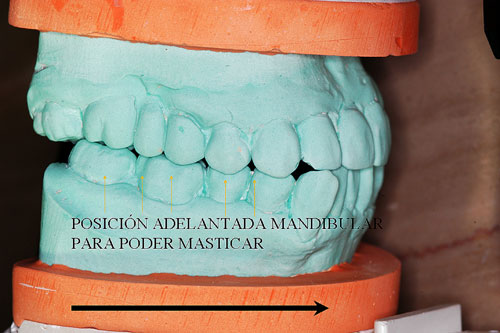

En este caso observamos que estando su ATM en Relación Céntrica, al cerrar la boca, solo un punto contacta del lado derecho del enfermo Punto Prematuro de Contacto), lo que hace imposible que con ese único punto desarrolle su función masticatoria y se vea obligado a mover su mandíbula hacia una posición de conveniencia, donde sean muchos más los puntos contactantes que mejoren el desgarro y aplastamiento de los alimentos.